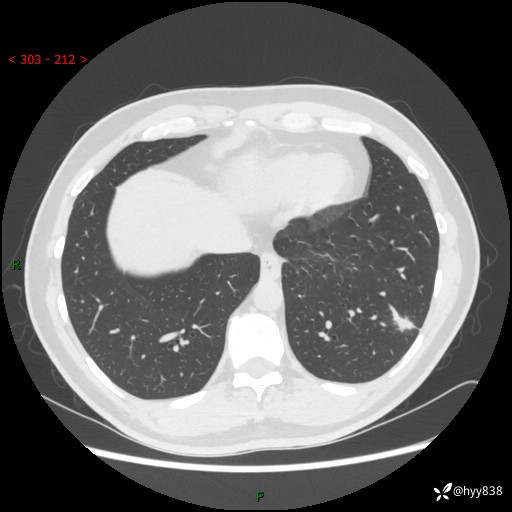

中年男性,胸闷3月余。多发团片、肺小叶分布、空气支气管征、明显强化---结果公布~

现病史:患者3月前出现胸闷,卧位时加重,坐位时缓解,无咽痛、咳嗽,无头痛,无全身酸痛,无结膜充血,无胸痛、心慌,无咯血,无呼吸困难,无咳痰,2024-07-02于当地市第一民医院行胸部CT,结果不详,2024-07-05就诊于我院急诊内科,行胸部CT同时增强,结果示:左肺下叶多发结节灶,考虑感染可能。今患者为求进一步诊治来我院,门诊以“肺部感染”收入我科。 患者本次起病来精神、食欲、睡眠尚可,大小便可,体力,体重无明显变化。

胸部CT平扫+增强

各期CT值:30hu 90hu 77hu